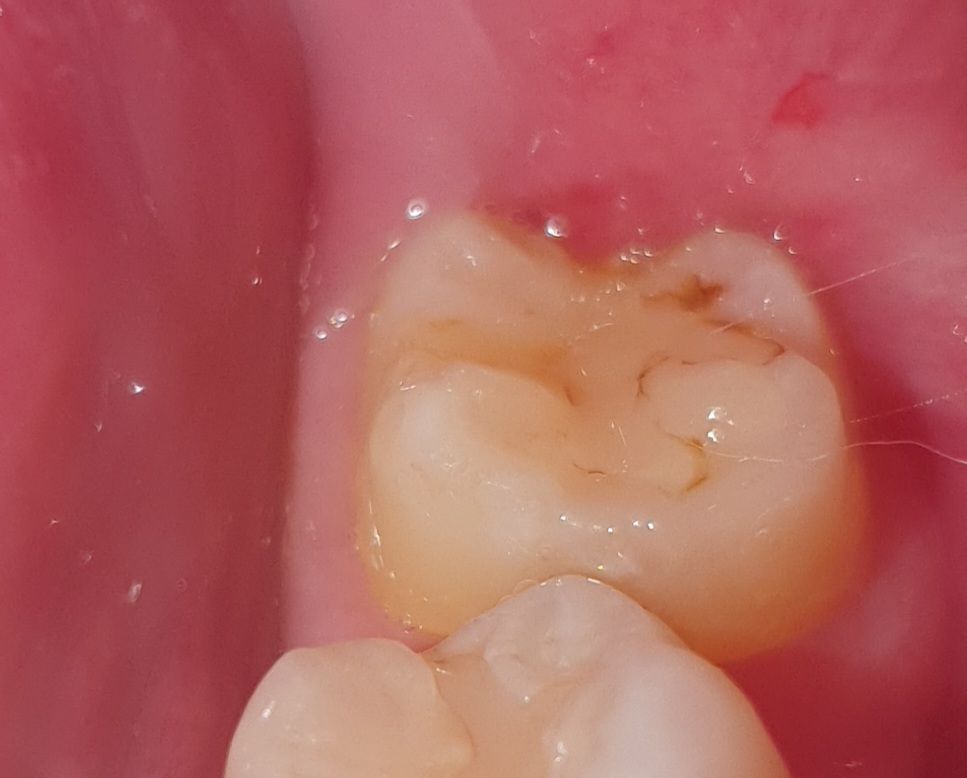

충치일까요? 충치라면 당장 치과에 가야할까요?

약 2달전에 교정 정기검진으로 치과를 갔다가 이번 5~6월쯤 다시 갈 예정인데

문듯 양치하다 거울을 봤더니 맨 안쪽 어금니가 이렇네요

아무래도 충치겠죠? 충치라면 나중에 치과를 갈때까지 치료를 미룰수 있을까요?

• 1번 째 사진

치아와 레진 사이에 충치 혹은 착색이 있어보이며 직접 검사를 해봐야 명확히 알 수 있겠습니다.

예전에 치료를 햇던곳 주변으로 착색 및 2차 충치가 생긴거 같습니다. 치과에 가셔서 검진을 받아보세요.

사진으로 봤을 경우에는 레진 충전물 주변으로 색상이 변화된 것으로 보입니다. 충치는 아닐 것으로 보이나 자세한 확인을 위해서 치과에서 진료를 받아보는 것을 권유드립니다.

현재 사진상 레진으로 떼운부위 주변으로 충치가 생긴것으로 보이며, 빠른시일내에 치과에 방문하여 상태를 확인하고 조기에 치료를 받길 권합니다.

기존에 떼운 재료의 변색, 착색 같습니다 만약 아무런 증상이 없다면 이차충치라는 근거는 엑스레이 찍어봐야 확인됩니다